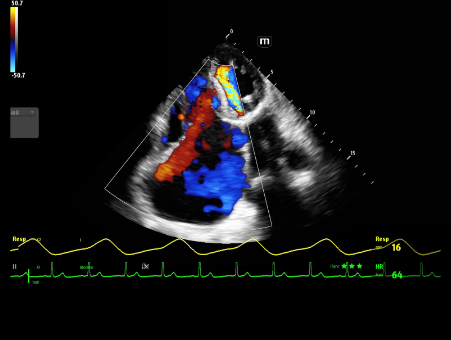

MindrayŌĆśs critical Ultrasound solutions drive improvements in care quality. Integrating advanced hemodynamic Ultrasound features, we can guarantee the highest standard of clinical care. The unique interoperability of Ultrasound and Vital sign data, we can provide comprehensive patient status data, to help inform clinical decisions, enhance clinical efficiency and, ultimately, improve patient outcomes.